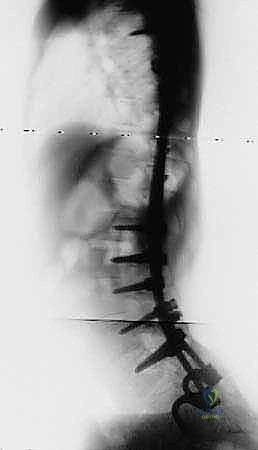

FIG 4 • Neuromuscular spinal deformity: spastic lordoscoliosis with S-hooks. These images demonstrate the long-term stability and correction achieved with S-rod fixation.